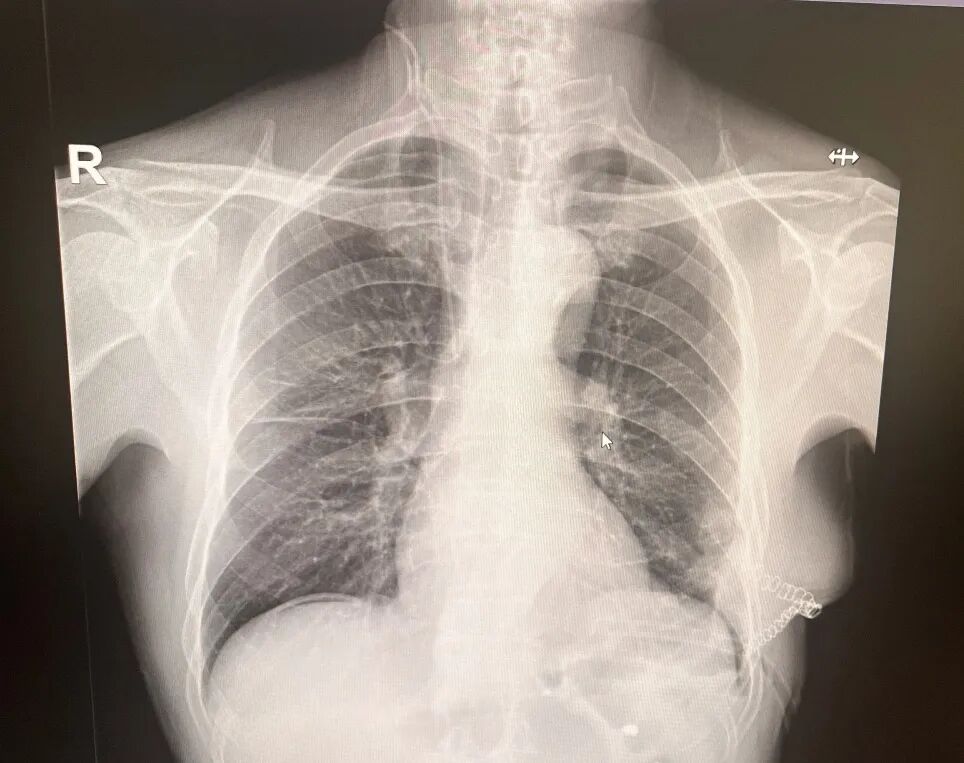

术后影像

膈疝修补如拆“定时炸弹”,需松解粘连、归位脏器、修复缺损三步精准到位。团队采用阶梯策略,在确保手术效果的同时最大程度降低风险、减少创伤。术后,刘大爷的症状迅速缓解,现已康复出院,重归正常生活。